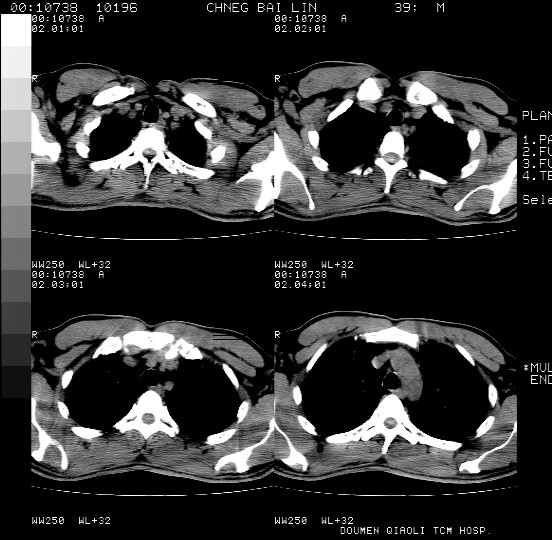

男,39岁。10天前自觉感冒,曾输液一次内容不详曾有吸毒史。现有咳嗽、咳痰胸闷。

双肺弥漫性网状、磨玻璃样病灶,边界不清。有吸毒史。首先考虑机遇性肺部感染。

两肺弥漫分布的网状毛玻璃状阴影,边缘模糊不清,纵隔未见明显淋巴结肿大

诊断:机遇性肺部感染

鉴别诊断:1特发性肺纤维化,主要部位在两肺下叶胸膜下网状,毛玻璃状及蜂窝状阴影,临近胸膜增厚,该病征象不太符合